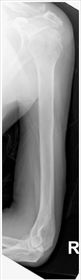

| AP Humerus | humeral epicodyles not in profile radial head, neck and tuberosity to not superimpose ulna arm is externally rotated (greater tubercle in profile) |

| AP Humerus | ANATOMY: entire humerus: shoulder -> elbow CRITERIA: greater tubercle in profile - hand externally rotated humeral epicondyles are parallel to IR POSITIONING: CR perpendicular @ midhumerus |